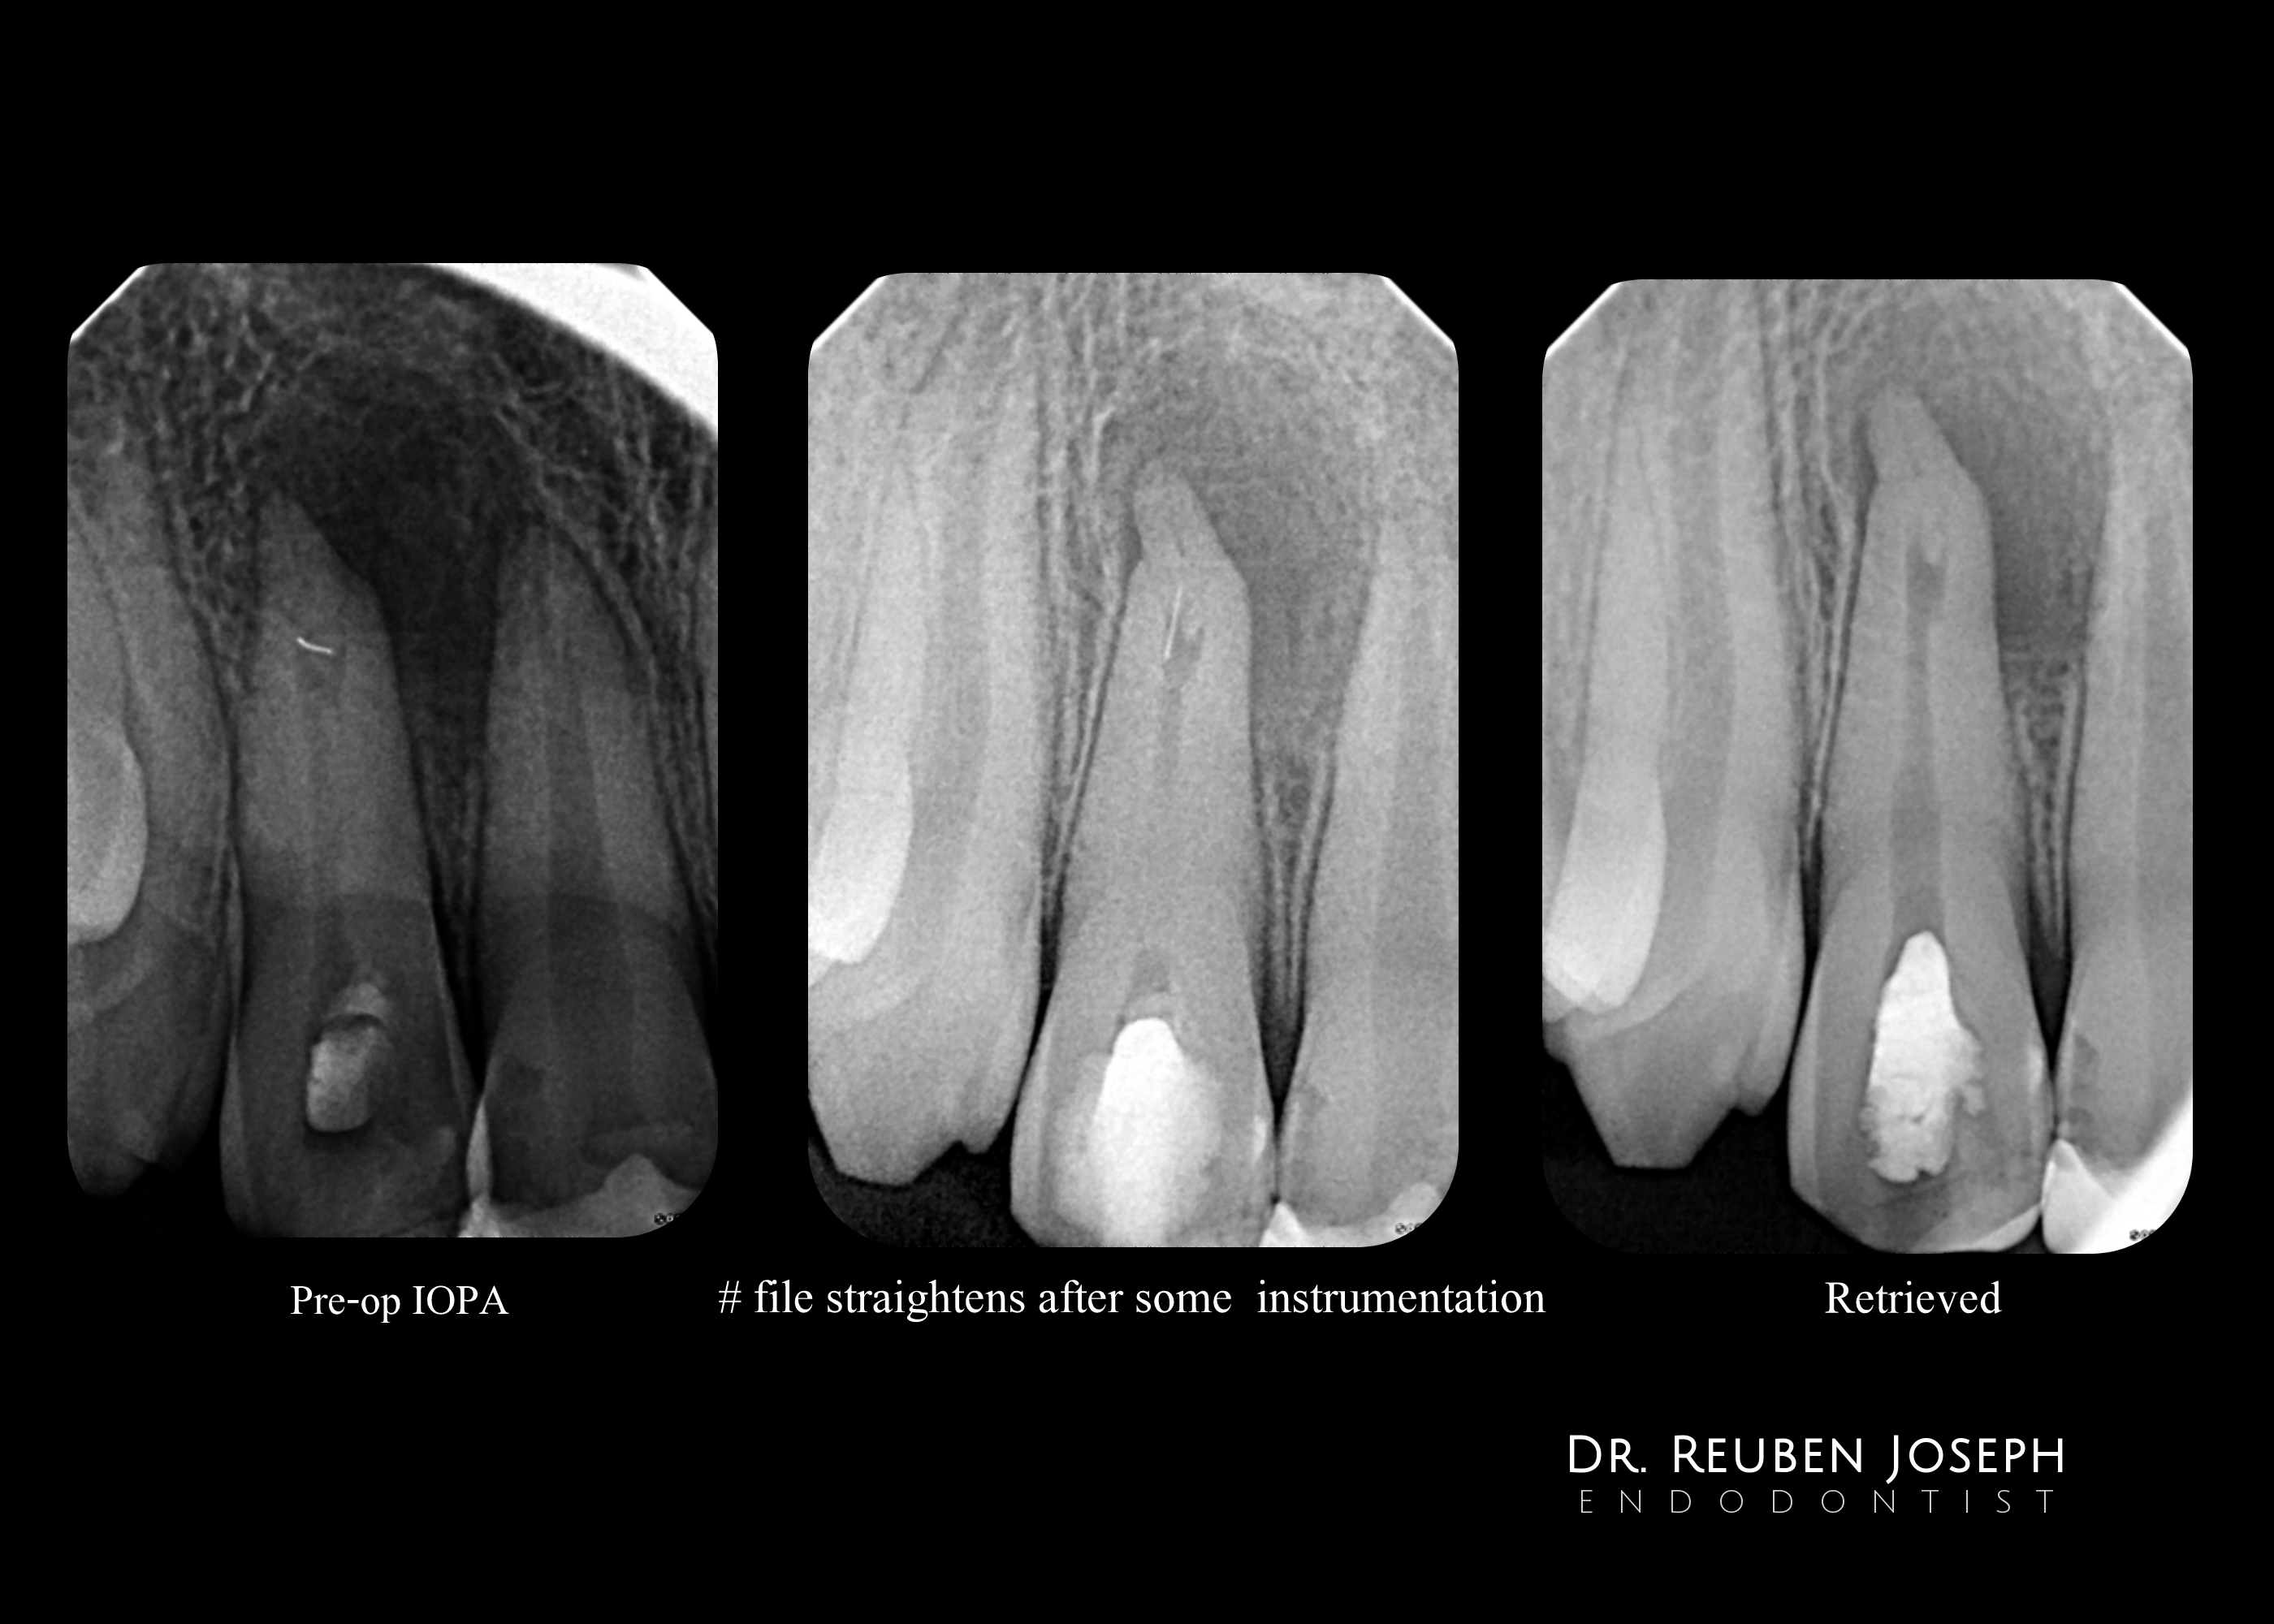

#7 referred with a separated file/internal resorption/calcification/apical split

Referring doctor had attempted an endo and separated an instrument

> Radiograph reveals

– Separated file lying horizontal in the internal resorptive defect

– A calcified mass of dentin within the resorptive defect

– An additional Canal present exiting laterally ?

PA lesion

– After a little fidgeting around with a U-file the separated instrument straightened up and retrieved